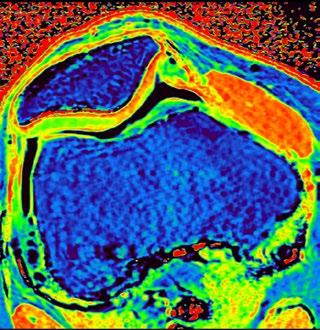

PD STIR - 1024 x 1024 matrix - 3mm slice thickness

Sag T2 - 0.5 x 0.5 min - 0:56 min Ax PD FatSat - 0.6 x 0.6 mm - 1:30 min Cor PD FatSat - 0.6 x 0.6 mm - 1:15 min Cor PD - 0.5 x 0.5 mm - 0:58 min © 2020 CANON MEDICAL SYSTEMS // MREU200040

Fast knee protocol with AiCE on Vantage Orian 1.5T